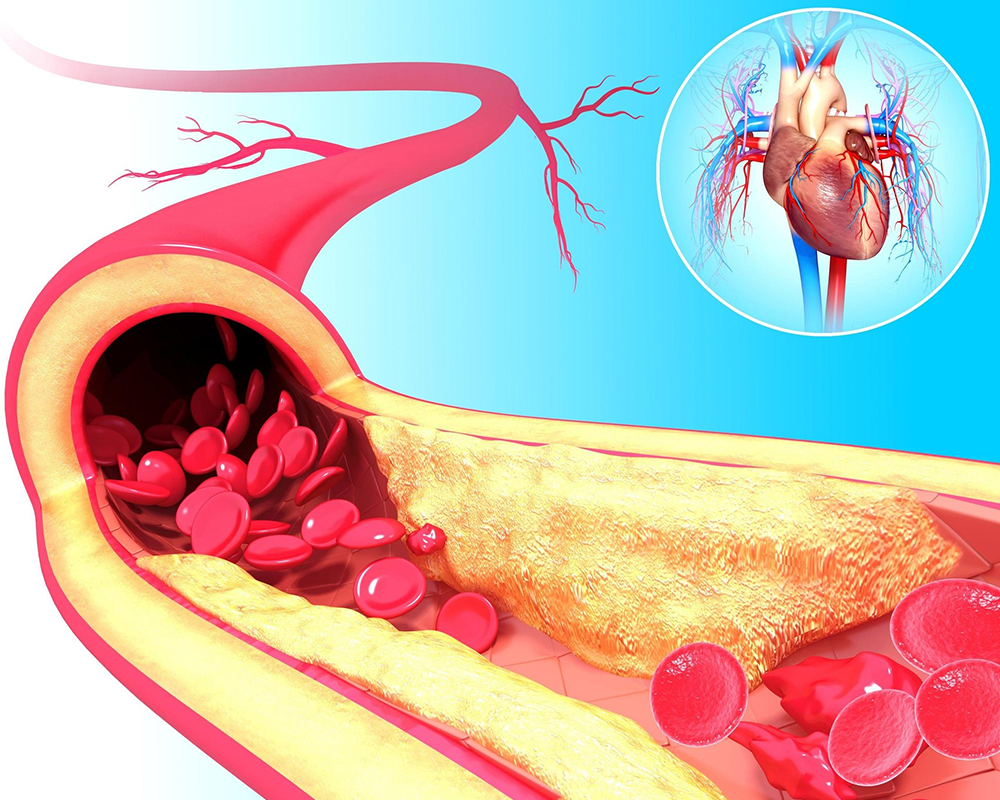

बाईपास सर्जरी और एंजियोप्लास्टी में क्या अंतर है?

आज के समय में दिल की बीमारियाँ आम समस्या बन गई हैं। गलत खान-पान, तनाव और जीवनशैली की वजह से दिल की धमनियों में ब्लॉकेज होना बहुत आम हो गया है। जब दिल तक खून की आपूर्ति प्रभावित होती है,

कोलेस्ट्रॉल और हार्ट अटैक का संबंध: समय पर सावधानी क्यों जरूरी है?

आज की तेज़ रफ्तार ज़िंदगी में हार्ट अटैक के मामले लगातार बढ़ते जा रहे हैं। खासकर युवाओं में दिल की बीमारी अब सामान्य हो गई है। इसकी सबसे बड़ी वजहों में से एक है कोलेस्ट्रॉल का बढ़ना। लेकिन क्या आप

बाईपास सर्जरी और एंजियोप्लास्टी में

आज के समय में दिल की बीमारियाँ आम समस्या बन गई हैं। गलत खान-पान, तनाव और जीवनशैली की वजह से दिल की धमनियों में ब्लॉकेज होना बहुत आम हो गया...

कोलेस्ट्रॉल और हार्ट अटैक का

आज की तेज़ रफ्तार ज़िंदगी में हार्ट अटैक के मामले लगातार बढ़ते जा रहे हैं। खासकर युवाओं में दिल की बीमारी अब सामान्य हो गई है। इसकी सबसे बड़ी वजहों...